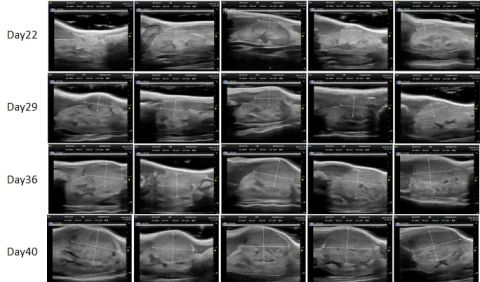

PDX Model (Growth Curve)

²¿·Ö×ðÁú¿Ê±PDXÔλģ×Óչʾ